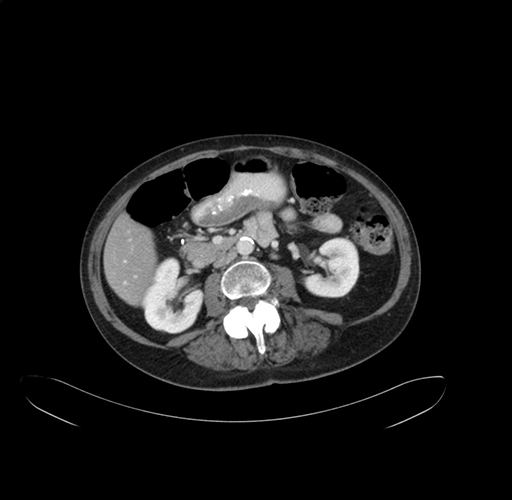

Pre-Chemo: Axial Venous

Axial Venous